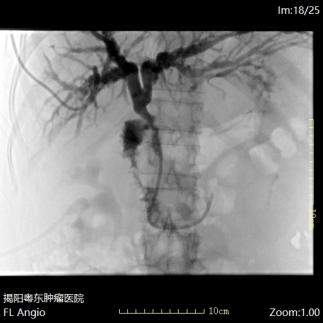

案例一:肝癌患者于外院治疗后复发,发现肿瘤新生血管。本院对其肝脏肿瘤进行血管介入治疗。在栓塞血管的基础上,同步注入高浓度化疗药物,形成 “血管栓塞 + 局部化疗” 的双重作用,直接杀灭癌细胞,疗效也更强。

案例一:肝癌供血血管影像

案例二:该名肝占位患者术中我院为其先行腹腔动脉造影,定位肿瘤供血血管。在造影过程中,发现胃十二指肠动脉与目标血管位置较近,为避免化疗药物误入非靶器官,遂先行栓塞该动脉。完成关键血管的栓塞后,随即将导管精准置入肝动脉,建立治疗通道。术后患者返回病房,经此留置的导管进行灌注化疗。通过术中栓塞保障了后续局部化疗的精准性与安全性,实现了对肿瘤细胞的持续、高效打击。

案例二:肝癌患者介入栓塞治疗前

案例二:肝癌患者介入栓塞治疗后